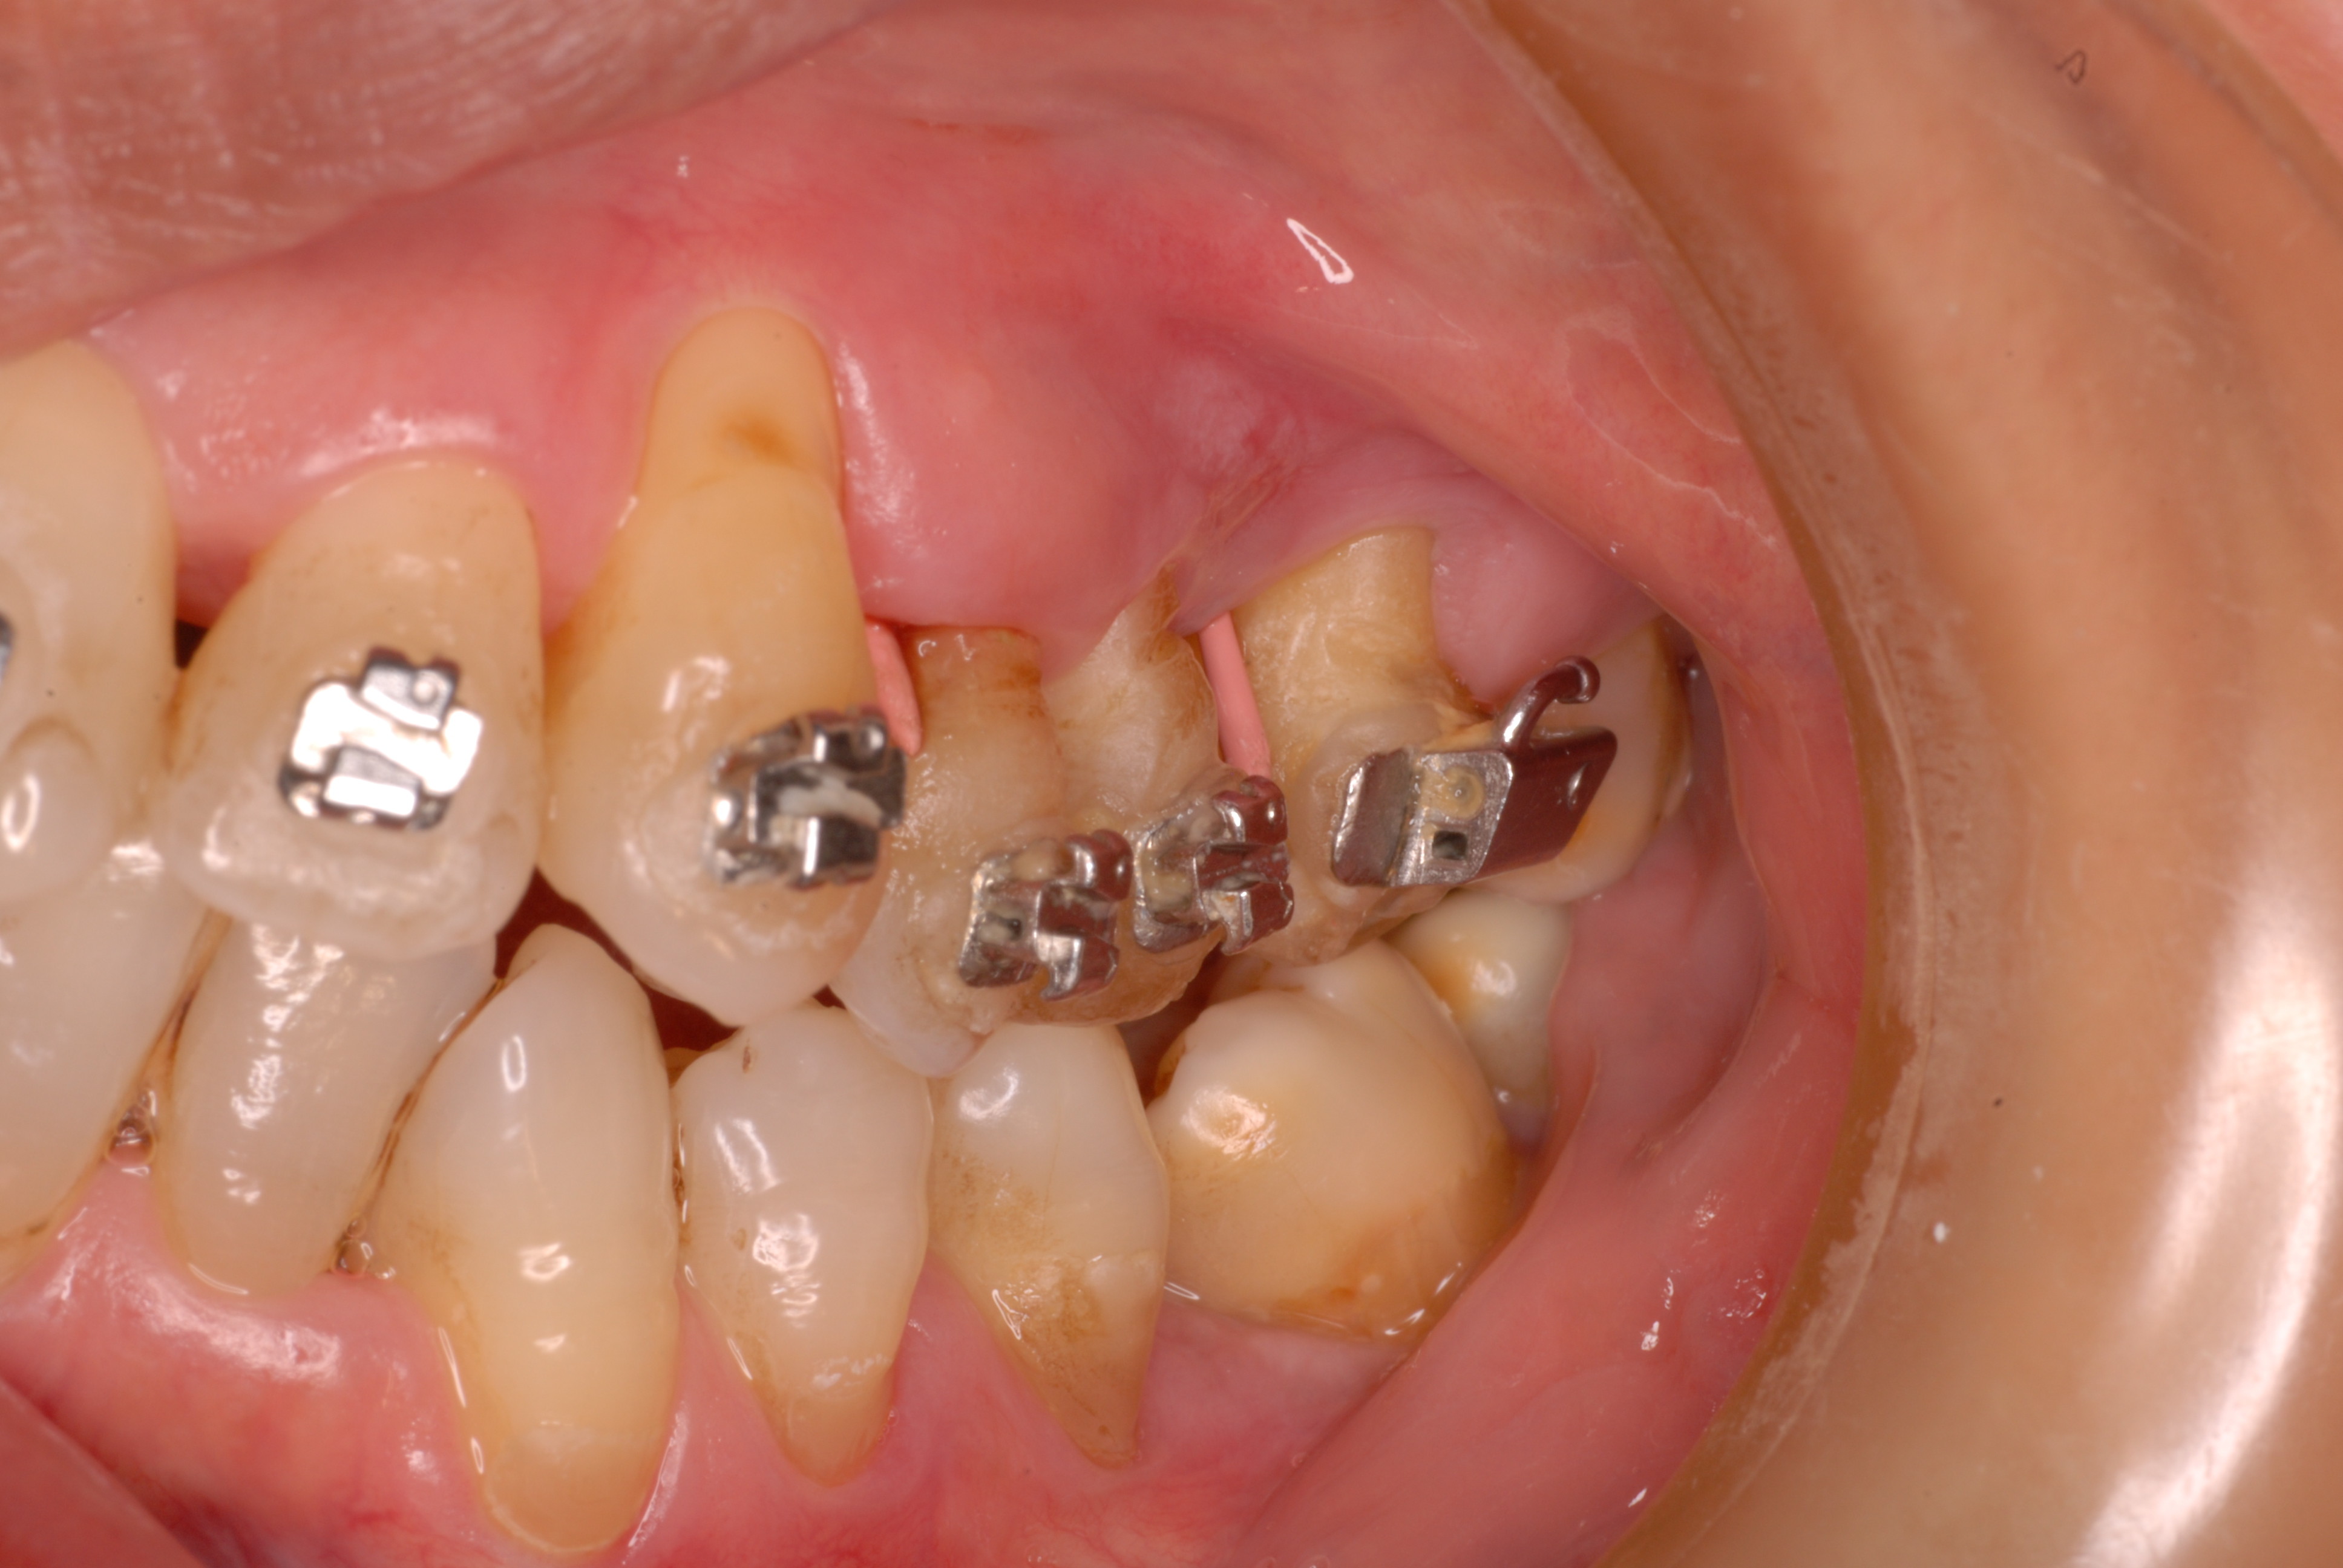

二ヶ月後ですが、歯周病が酷くなったので一時的に矯正治療を中止しました。歯周ポケットの深さを測っています。

挿入したゴムのポイントです。

歯並びは綺麗になり掃除はしやすくなったはずですが、矯正治療中は

磨きにくいので歯周病や虫歯が酷くなりやすいのです。